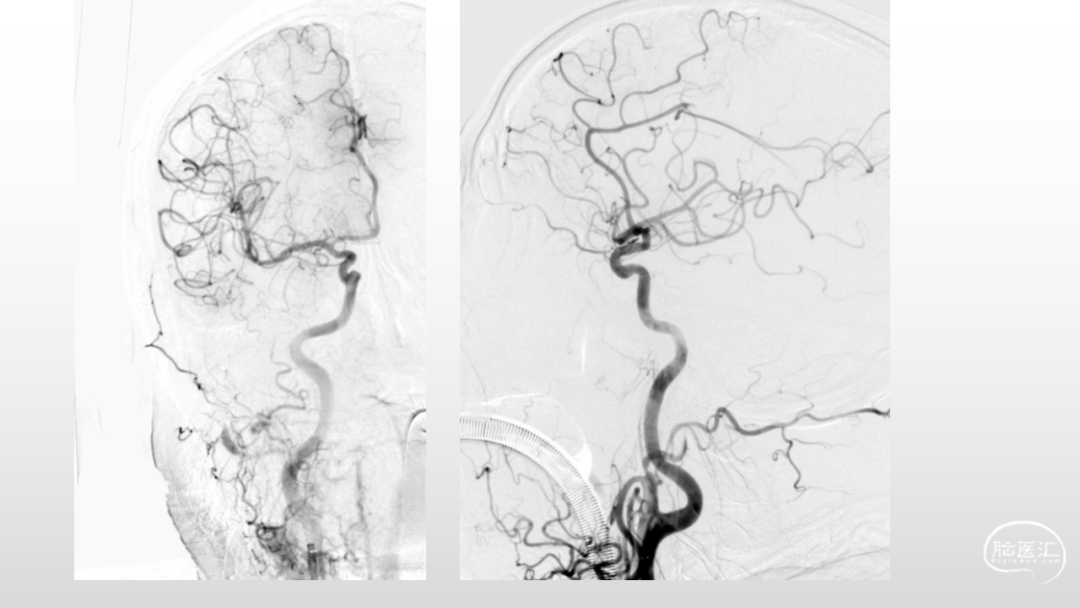

取之有道·第54期|李子付:Flowgate2取栓应用

看李子付解“取之有道”

滑动浏览更多内容